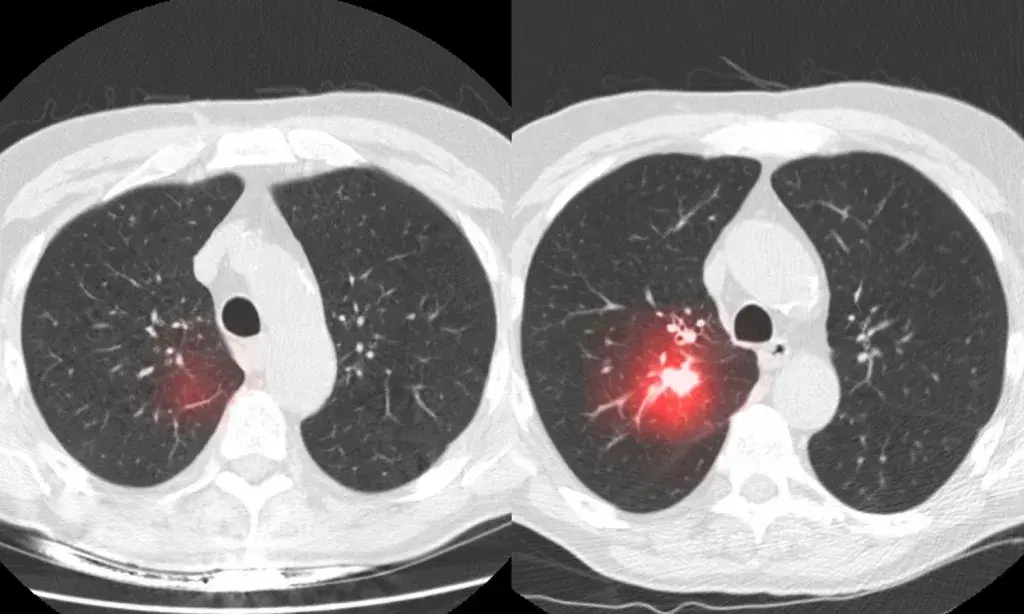

Researchers at Mass General Cancer Center and MIT (Massachusetts Institute of Technology) developed and tested an AI tool called Sybil. Sybil is trained in low-dose chest CT scans and is designed for individuals aged 50 to 80 years who have a significant smoking history or are smokers at present.

When it came to lung cancer screening, Sybil demonstrated the ability to evaluate pictures and precisely predict a patients risk of developing the disease during the next six years.